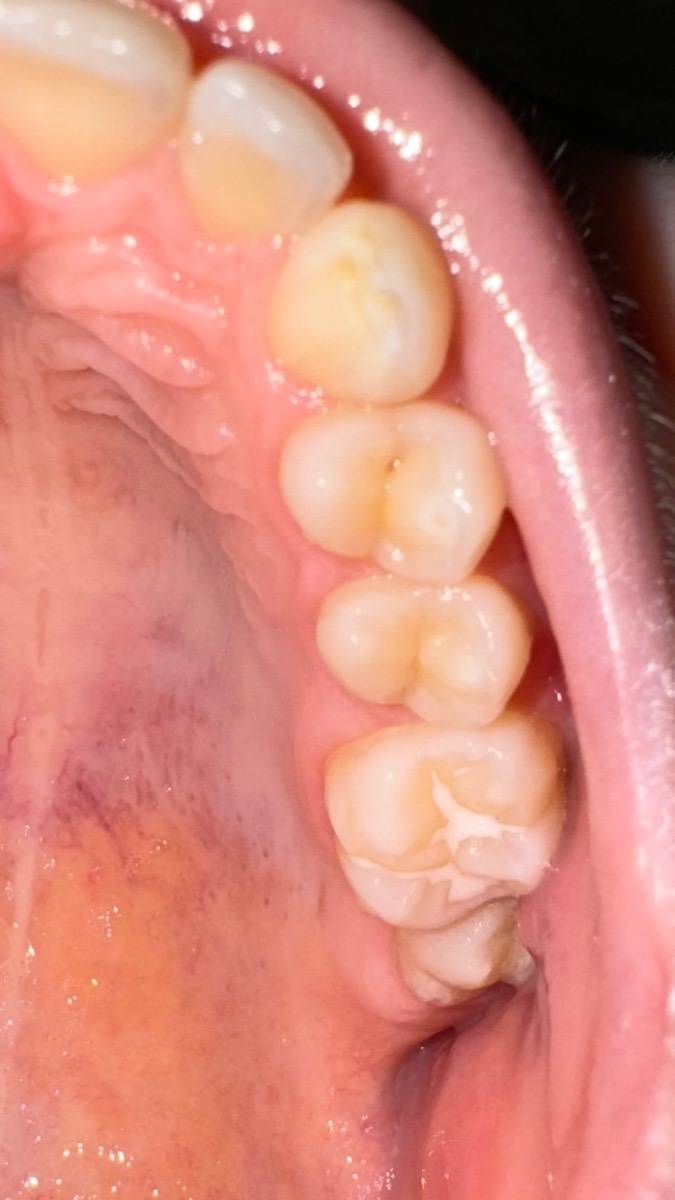

Ольгаxxx Опубликовано 16 июня, 2025 Поделиться Опубликовано 16 июня, 2025 Уважаемые стоматологи, подскажите, пожалуйста, это у ребёнка кариес на двух четверках? 😱 Ребёнку 14, через пару месяцев 15 лет. Можно ли после лечения их потом закрыть герметиком? Или пломба уже будет служить герметиком 😔? Подростку какую проф гигиену выбрать? В ноябре 2024 г. у ребёнка была проф гигиена, но я даже не спросила каким средством почистили. Мое упущение. А кариес на 4 ках - какую пломбу лучше выбрать, на что обратить внимание? Сердечная благодарность за Ваши ответы! Ссылка на комментарий

red_butler Опубликовано 17 июня, 2025 Поделиться Опубликовано 17 июня, 2025 Здравствуйте, на фото кариес не вижу, вижу пигментированные фиссуры, сходите на очный осмотр Ссылка на комментарий

red_butler Опубликовано 17 июня, 2025 Поделиться Опубликовано 17 июня, 2025 59 минут назад, Ольгаxxx сказал: Уважаемый доктор, мы сходим, только, скажите, пожалуйста, нужно ли ребёнку провести проф гигиену глицином? Гигиенист может ли убрать пигмент? Не вижу на фото показаний к профессиональной гигиене, можно попробовать очистить фиссуры содоструем, и после этого принимать решение о мини ивазивном лечении 1 Ссылка на комментарий